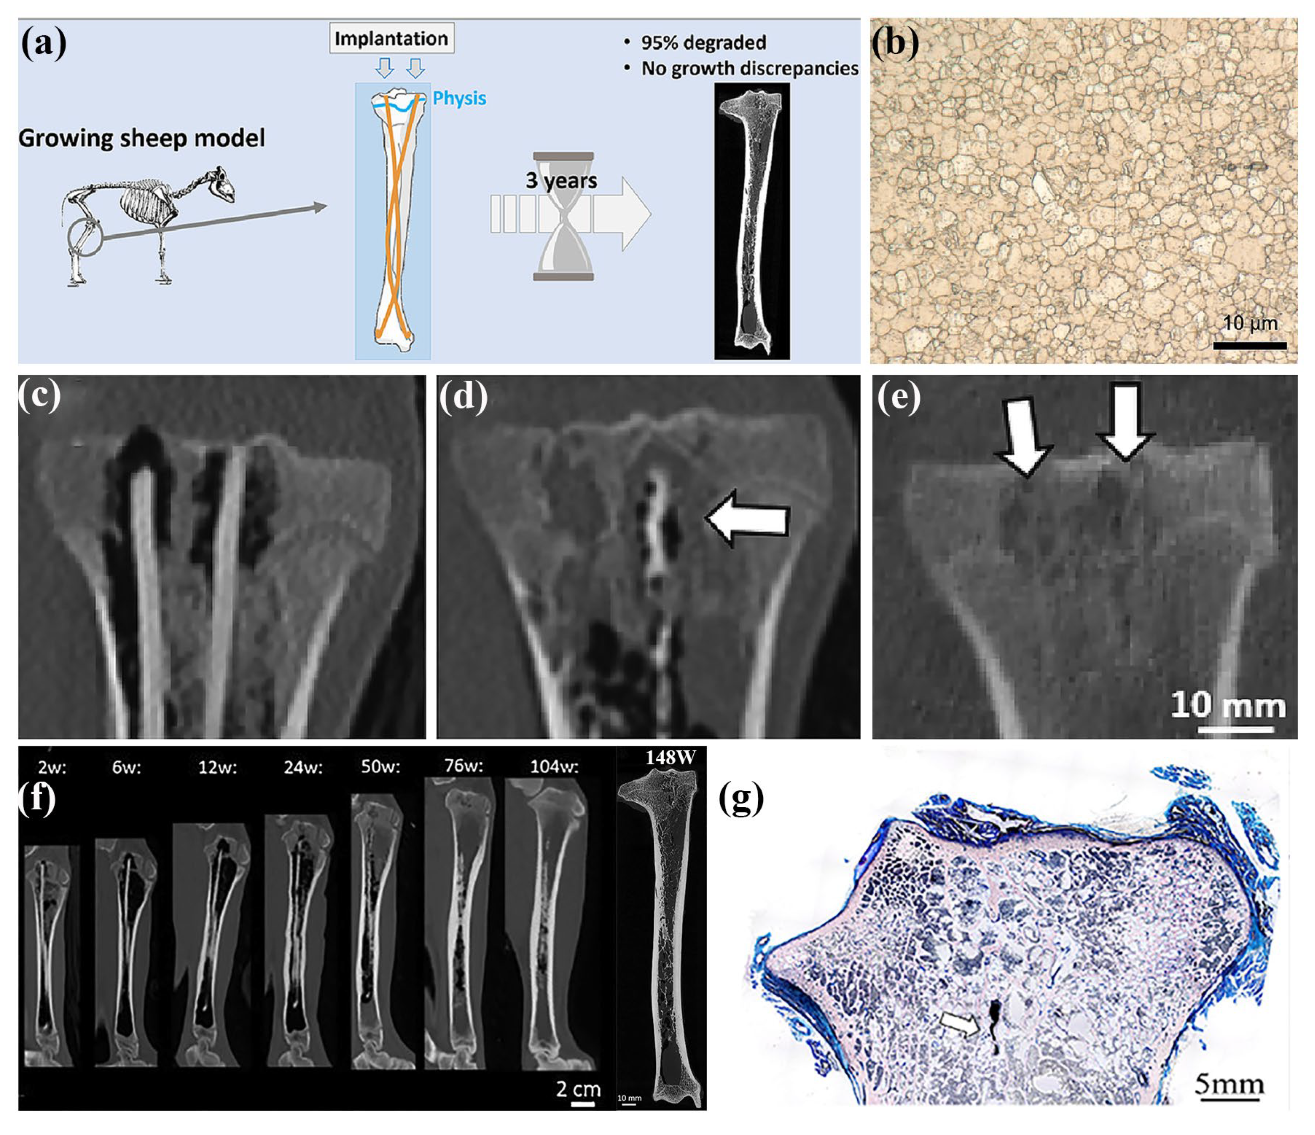

3.4. Intramedullary Nail

- Marek, R.; Eichler, J.; Schwarze, U.Y.; Fischerauer, S.; Suljevic, O.; Berger, L.; Loffler, J.F.; Uggowitzer, P.J.; Weinberg, A.M. Long-term in vivo degradation of Mg-Zn-Ca elastic stable intramedullary nails and their influence on the physis of juvenile sheep. Biomater. Adv. 2023, 150, 213417. [Google Scholar] [CrossRef] [PubMed]